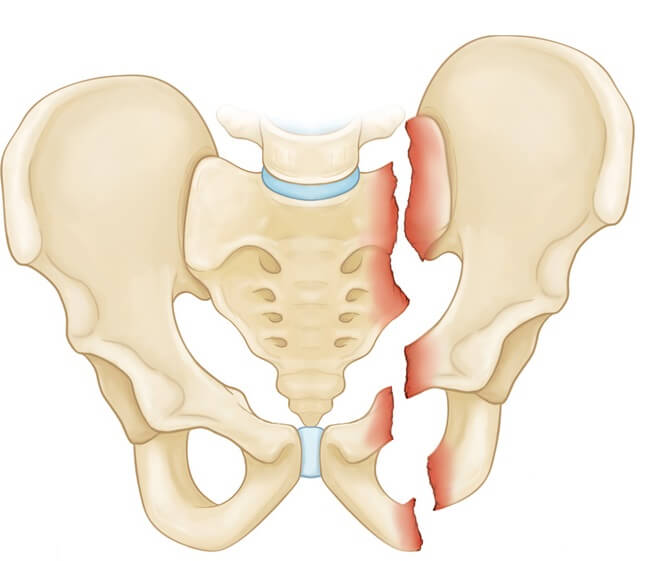

Односторонний перелом седалищной и лонной костей таза

Двусторонние переломы лонной и седалищной костей